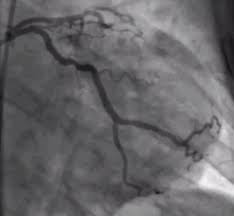

관상동맥 질환이란?

관상동맥 질환은 심장 근육으로 혈액을 공급하는 관상동맥(심장동맥)의 퇴행적인 변화로 인해 발생하는 질환의 집합을 나타냅니다. 이 질환은 주로 동맥 내벽에 지방과 칼슘이 쌓이고 염증이 발생하여 동맥이 협착되거나 막히는 상태를 말합니다. 관상동맥 질환은 주로 관상동맥경화증(관상동맥동맥경화증)과 안정형 협심증, 불안정형 협심증, 심근경색증으로 나뉩니다.